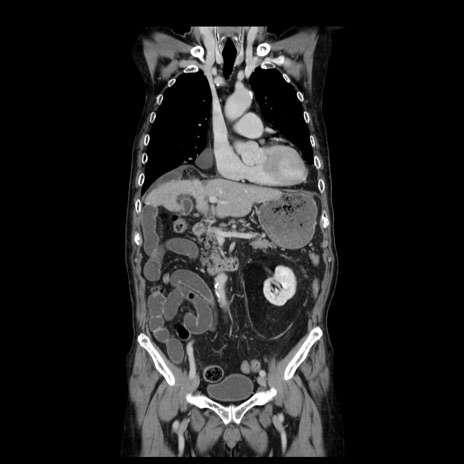

症例21(冠状断像)

【症例】70歳代男性

【主訴】腹痛

【現病歴】肝硬変・肝細胞癌にてかかりつけの方。約9時間前に食後より腹痛出現。症状が徐々に増悪し、嘔吐出現したため来院。

【既往歴】肝硬変、肝細胞癌(RFA、TACE後)

【身体所見】意識清明、表情苦悶様、BT 36℃、BP 129/78mmHg、P 88bpm、SpO2 97%(RA)、右上腹部から心窩部にかけて圧痛あり、反跳痛なし、筋性防御あり。

【データ】WBC 5800、CRP 0.16